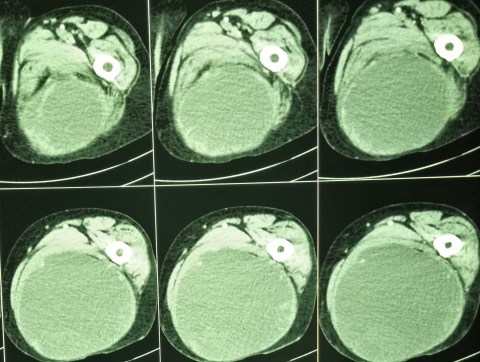

12.3.18

A presumed abscess of the thigh ( huge in size, diagnosed clinically and confirmed on CT scan) drained in an elderly ( 60 years old) female. The fluid was largely serous with lots of flakes. When examined after a month or so, the wound had partially healed but the cavity was filling up with a fleshy growth. Was referred to PGI where a high-grade soft-tissue sarcoma was diagnosed. She died soon after.